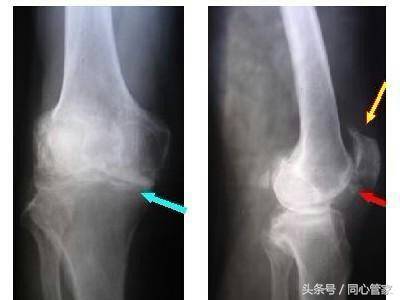

8、骨刺—是人体的自我保护

大多数人一听到有“骨刺”就立即想到拔刺,欲把刺弄掉而后快。甚至常常会和“骨裂”联系到一起,担心是不是“骨裂”导致的细小“骨刺”?大家完全被“骨刺”的名字欺骗了,骨刺其实是一种人体的自我保护。

广州中医药大学骨伤科医院骨伤三科主任医师张文财介绍,骨刺即骨质增生,是人体的一种自我保护反应,也不是引起疼痛的主要原因,而且大多数骨刺并不用治疗,要治的话就只能治引起骨刺的原发病——骨性关节炎,比如进行减肥、选择合适的运动方式,以及药物止痛等。